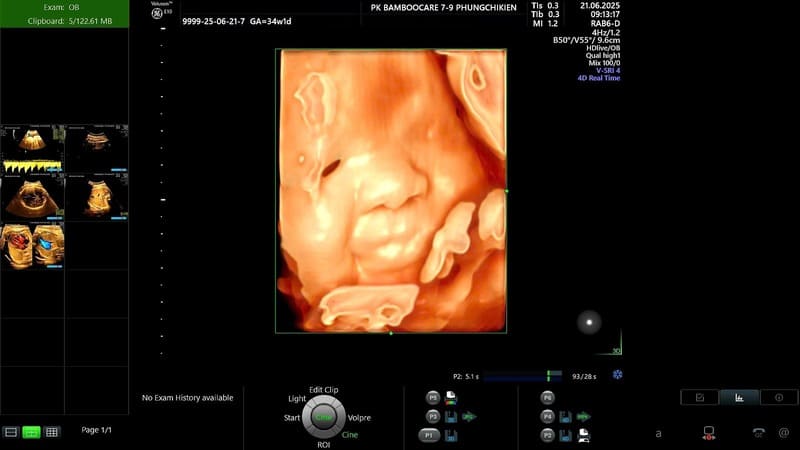

Bạn đang tìm kiếm một địa chỉ siêu âm uy tín để theo dõi thai kỳ? Phòng Khám Sản – Phụ Khoa Bamboo Care mang đến dịch vụ Siêu âm thai 5D tại Vinh uy tín và chất lượng, giúp mẹ bầu an tâm đồng hành cùng con yêu với hình ảnh sắc nét và kết quả chẩn đoán chính xác.

Bamboo Care ứng dụng công nghệ siêu âm 5D hiện đại, mang đến hình ảnh thai nhi sắc nét và sống động. Mẹ bầu có thể dễ dàng quan sát khuôn mặt, tay chân, thậm chí cả biểu cảm nhỏ của bé ngay trong bụng mẹ. Đây không chỉ là bước kiểm tra y khoa mà còn là trải nghiệm đầy cảm xúc cho gia đình. Nhờ chất lượng hình ảnh vượt trội, nhiều mẹ đã tin tưởng lựa chọn dịch vụ siêu âm thai 5D tại Vinh tại Bamboo Care để lưu giữ những khoảnh khắc đáng nhớ này.

Một ưu điểm nổi bật của siêu âm 5D là khả năng hỗ trợ chẩn đoán sớm các bất thường bẩm sinh như sứt môi, dị tật tim hay bất thường ở tay chân. Hình ảnh chi tiết giúp bác sĩ đánh giá chính xác sự phát triển toàn diện của thai nhi qua từng giai đoạn. Với đội ngũ bác sĩ giàu kinh nghiệm, Bamboo Care luôn mang đến kết quả tin cậy, kịp thời tư vấn và theo dõi sát sao. Chính vì thế, dịch vụ siêu âm thai 5D tại Vinh của Bamboo Care được nhiều mẹ bầu lựa chọn để an tâm đồng hành suốt thai kỳ.